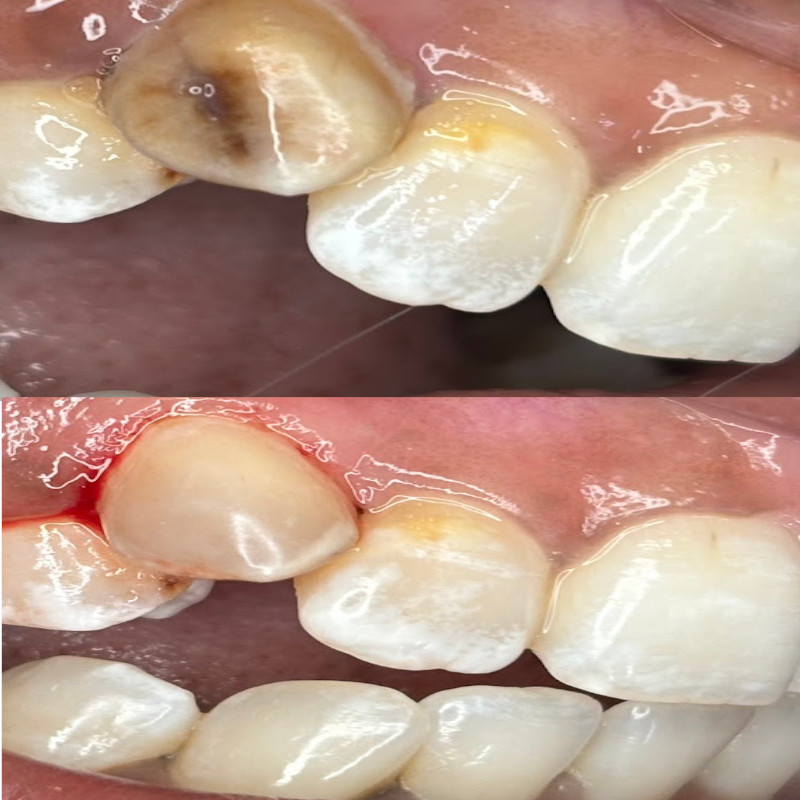

Complex Restoration

- INFO:

Multi-stage treatment with RCT, post and crown for broken fluorosed tooth